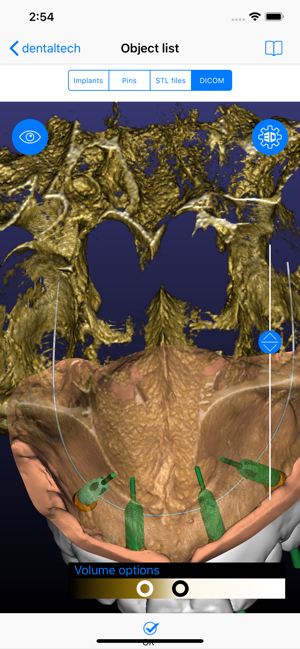

ICX-Magellan X is a cloud-based Software concept used for CBCT-Analysis and to create Implant-Treatment plans.

The ICX-Magellan X App completes this System primarily regarding communication, treatment-plans that were prepared at the pc can be shared with other users in real-time, commented, changed or confirmed.

The App can be integrated supporting any workflow; existing treatment-plans can be recalled, edited or used for patient-education anywhere anytime.